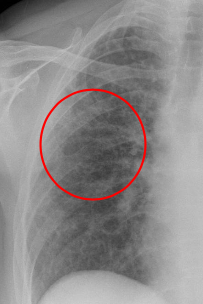

Patrón de vidrio esmerilado / despulido IMAGEN

Puedo ver los vasos sanguíneos en opacidad